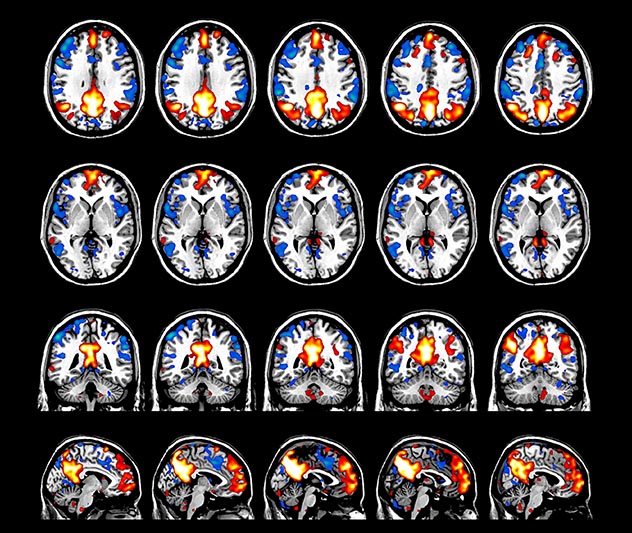

The fMRI pulse sequence was a single shot FFE echo planar acquisition using MultiBand SENSE factor 5, dS SENSE factor 1.25, isotropic voxel size 2.7 mm, 50 transverse slices, TR 700 ms, TE 30 ms, flip angle 52 degrees, 765 dynamic scans, total scan duration 9:01 minutes. Image provided by Matthan Caan, PhD, Assistant Professor at the AMC.

Default mode network as discovered by resting state fMRI in one participant of the ALFA cohort [7]. rs-fMRI allows us to find networks of brain regions with highly correlated activity and sustaining distinct brain functions. The default mode network (in warm color scale) is active when the brain is focused on introspective thinking and has been shown to be altered in Alzheimer’s. Interestingly, brain areas of this network are known to show abnormal levels of one of the pathological hallmarks of Alzheimer’s (b-amyloid deposition) in preclinical stages. We want to better understand the alterations of these brain networks in preclinical stages of Alzheimer's and explore their potential use as biomarkers.

Imaging was performed using Ingenia 3T CX with a 32ch dS Head coil, TR 1.6 sec, TE 35 ms, voxel size 3.1 x 3.1 x 3.1 mm, 46 slices and Multiband SENSE factor 2. Image provided by Dr. Gispert